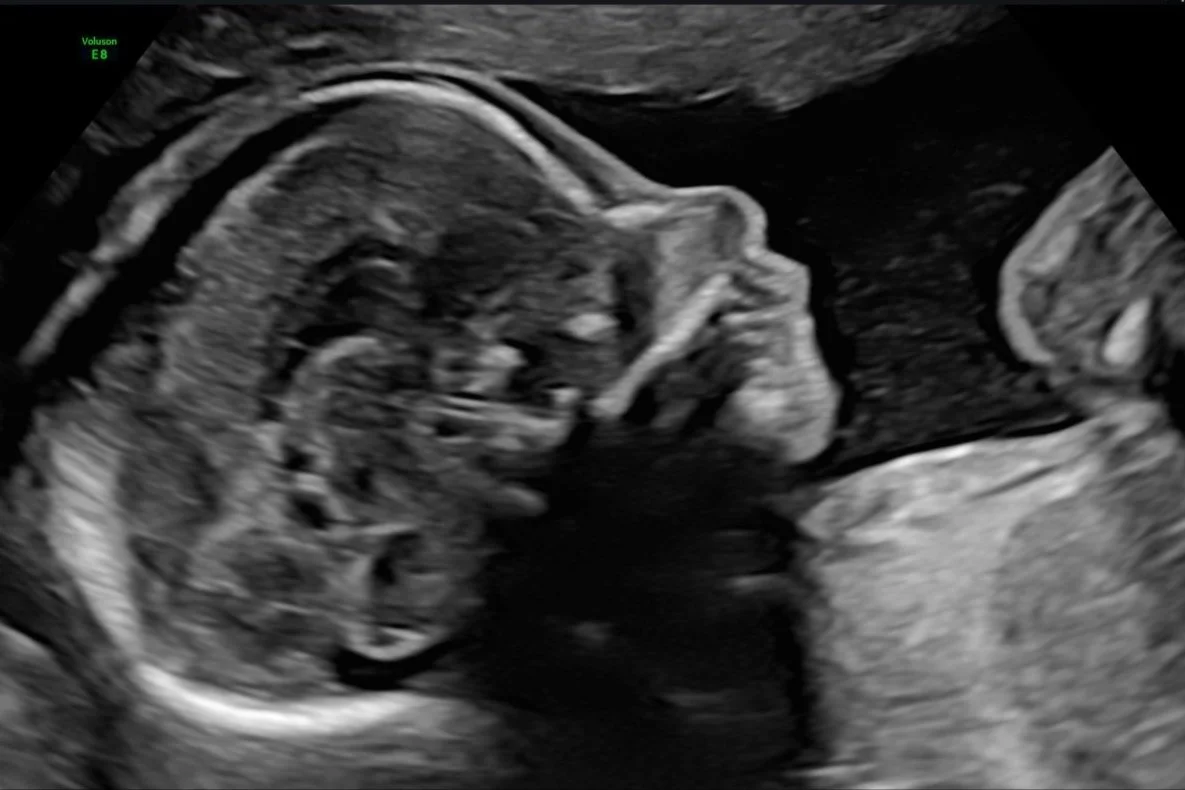

A routine Ultrasound examination is offered to most women at 19-22 weeks. This scan is often referred to as a Morphology or 20 week ultrasound.

- Perform a detailed assessment of the developmental anatomy of the fetus’ head, brain, face, lips, palate, heart, diaphragm, lungs, kidneys, abdominal wall, bladder, spine, skin line, arms, hands, legs and feet.

Our Morphology Scans take up to 50 minutes and include:

- 2 x 3D thermal printed hard copy images

- All pictures taken on the day straight to your mobile phone